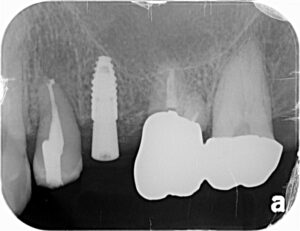

埋入は骨のある部分に行いましたので 、安全に行えます。抜歯窩は少し削って親知らずが埋まるような穴をあけます。

歯が入った時の写真です。抜歯から約9ヶ月で完成です。